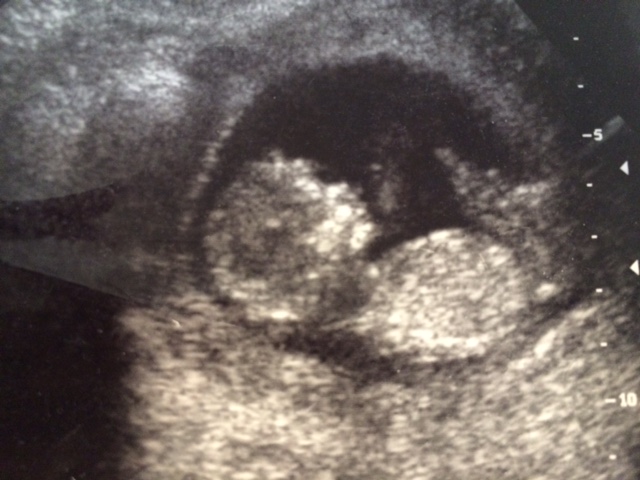

Hi, this is a picture of my 13 week abdominal ultrasound. Any guesses based on skull theory? I don't think that this picture is clear enough for nub theory guesses....

Thanks.